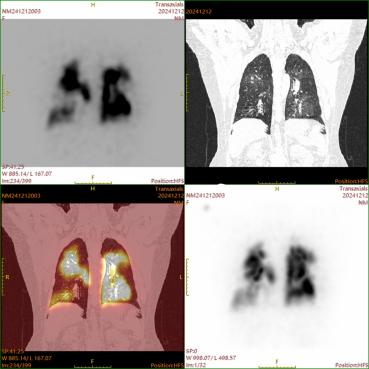

典型病例

核医学肺灌注平面显像+SPECT/CT断层融合显像示双肺多发肺栓塞。

图片